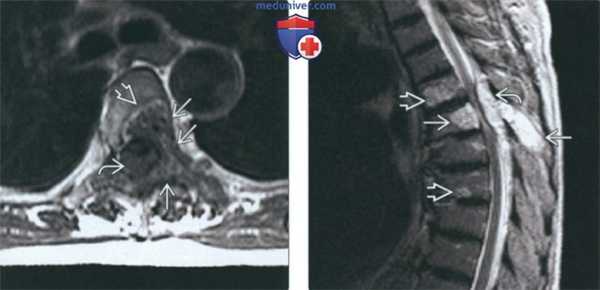

(Слева) Рентгенография в косой проекции: патологический очаг крыла подвздошной кости с периостальной реакцией по типу солнечной вспышки. Такой характер периостальной реакции чаще всего наблюдается при гемангиомах черепа, но может встречаться и при любой другой локализации.

(Справа) КТ, аксиальная проекция, без контрастного усиления: у этого же пациента реакция по типу солнечной вспышки отмечается в той части гемангиомы, которая распространяется на переднюю поверхность крыла подвздошной кости. В своем основании, в крыле подвздошной кости, патологический очаг имеет характер пчелиных сот. (Слева) МРТ, аксиальная проекция, режим Т2: у этого же пациента патологический очаг и его переднее расширение характеризуется сигналом более высокой интенсивности, однако в структуре очага визуализируются признаки низкоинтенсивной костной реакции.

(Справа) МРТ, аксиальная проекция, режим Т1, с контрастным усилением: патологический очаг накапливает контрастное вещество и характеризуется низкоинтенсивной реакцией кости по типу пчелиных сот и солнечной вспышки. Экспансивный очаг окружен кортикальным слоем, мягкотканный компонент отсутствует. Подвздошно-поясничная мышца растянута и смещена кпереди и кнутри. (Слева) Рентгенография в боковой проекции: хорошо отграниченный очаг, имеющий структуру по типу пчелиных сот. Обратите внимание на то, что наружная пластинка поражена в большей степени, чем внутренняя. В литературе часто описывается структура новообразования по типу солнечной вспышки, однако очаги по типу пчелиных сот могут встречаться чаще.

(Справа) МРТ, аксиальная проекция, режим Т2: резко очерченная экспансивная гемангиома, характеризующаяся структурой по типу пчелиных сот, обусловленной внутридиплоитическим утолщением трабекул. Наружная пластинка поражена в большей степени, чем внутренняя.